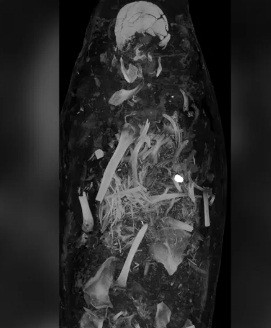

Cụ thể, 2 xác ướp được quấn một lớp vải trước khi bao bọc bằng một lớp ván gỗ cực mỏng. Trên bề mặt của lớp ván gỗ là chân dung của người quá cố.

Thêm nữa, 2 xác ướp còn được trang trí bằng thạch cao và vàng. Nhà Ai Cập học Stephanie Zesch cho hay hai xác ướp gồm 1 nam và một nữ.

Bên cạnh 2 xác ướp, giới nghiên cứu còn tìm thấy một số cổ vật khác như vòng cổ và tiền xu. Trong số này, tiền xu được cho là để người chết dùng trả cho thần Charon. Vị thần này chuyên chèo thuyền đưa linh hồn của người quá cố qua sông Styx đến thế giới bên kia.

Với những món đồ tùy táng được tìm thấy cùng lớp vải niệm đặc biệt như trên, các chuyên gia suy đoán hai người này có thể đến từ tầng lớp có địa vị cao trong xã hội.